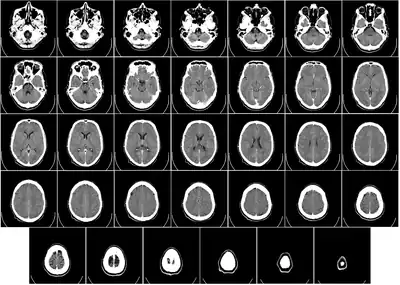

T1-weighted MRI scans (with contrast) of the same brain slice at monthly intervals. Bright spots indicate active lesions of multiple sclerosis.

Photo credit: Public domain (U.S. Brookhaven National Laboratory)